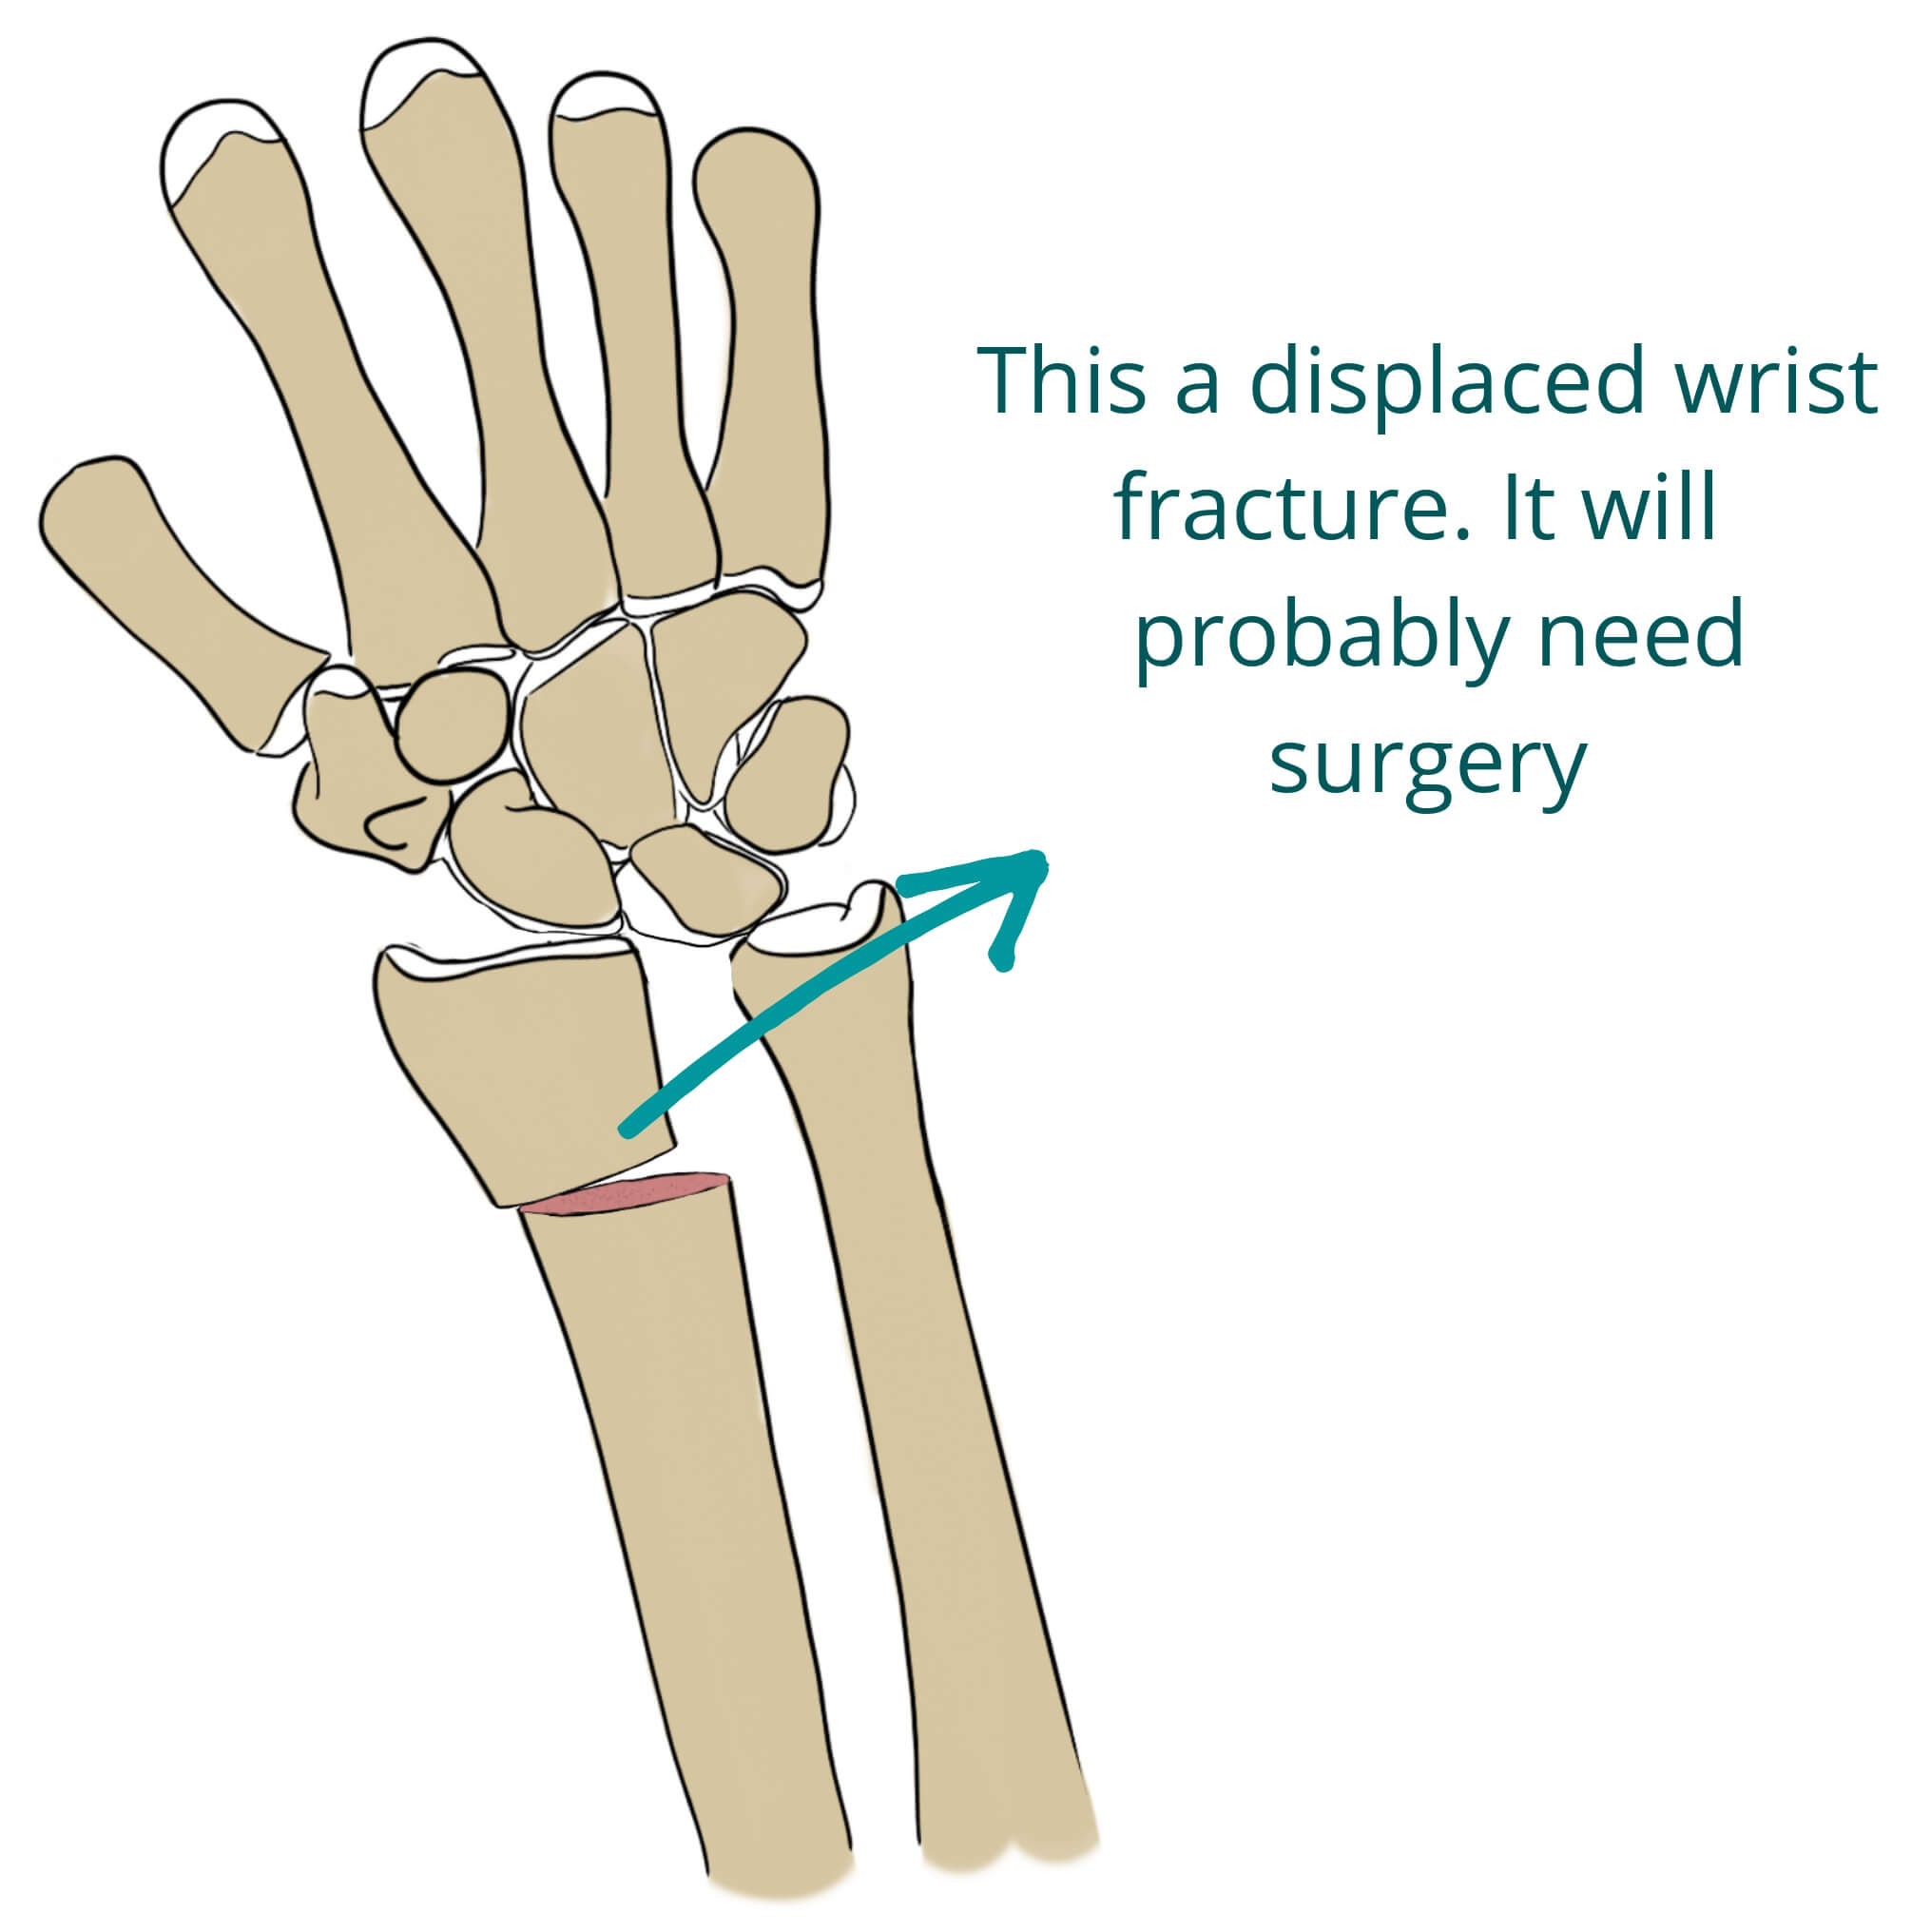

Types Of Wrist Fractures – Fracture Treatment

Broken Wrist Treatment | Wrist Fracture Treatment

What is Closed Fracture of the Wrist, Know its Treatment, Recovery …

Wrist Fractures (Distal Radius Fractures) – Pro doctor

Wrist Fractures (Distal Radius) – Hobart Orthopaedics

What Is A Wrist Fracture?

Colles’ Fractures (Broken Wrist) | Florida Orthopaedic Institute

Distal radius fracture: causes, symptoms, conservative and surgical …